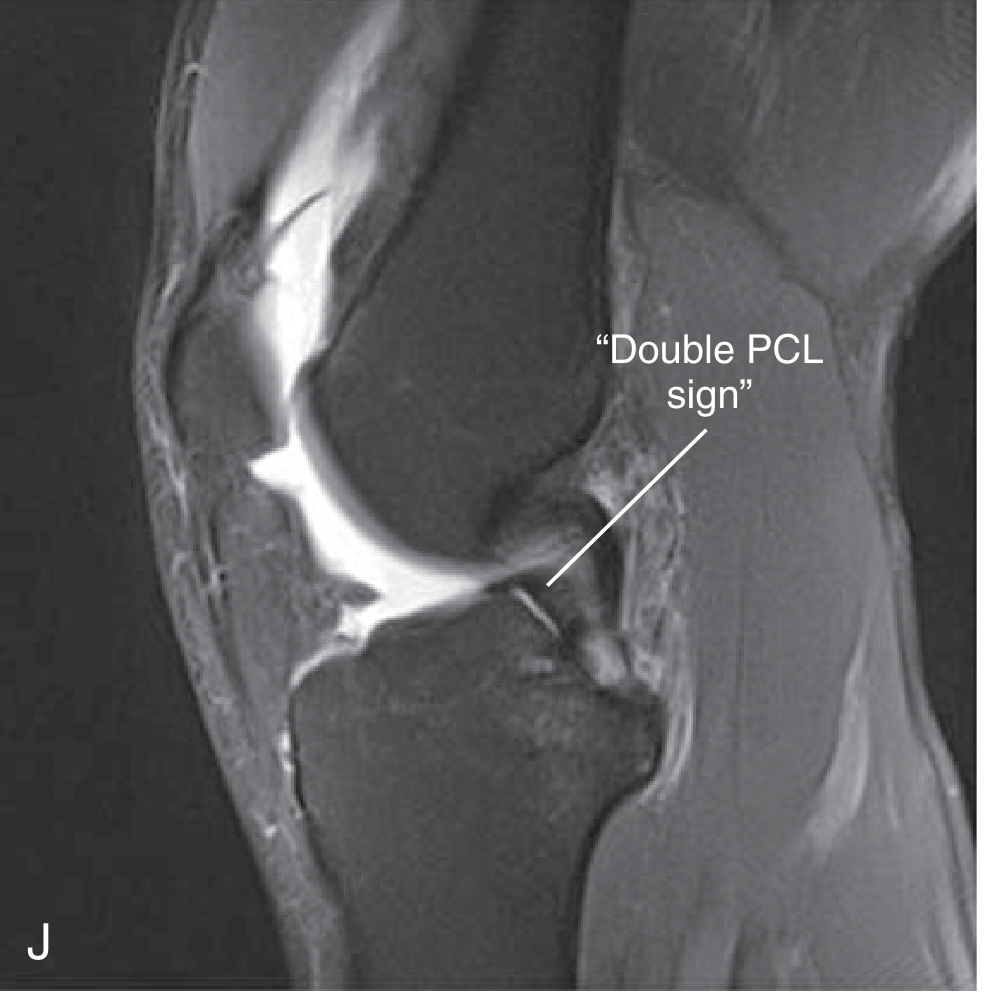

Double PCL Sign (Sagittal)

The displaced fragment lies in the intercondylar notch anterior and inferior to the PCL, creating a second band paralleling the PCL on sagittal views.

Sagittal MRI — "Double PCL sign" with displaced bucket-handle fragment lying parallel to and below the PCL

Bucket-handle medial meniscus tear — Double PCL sign (Miller's Review of Orthopaedics)